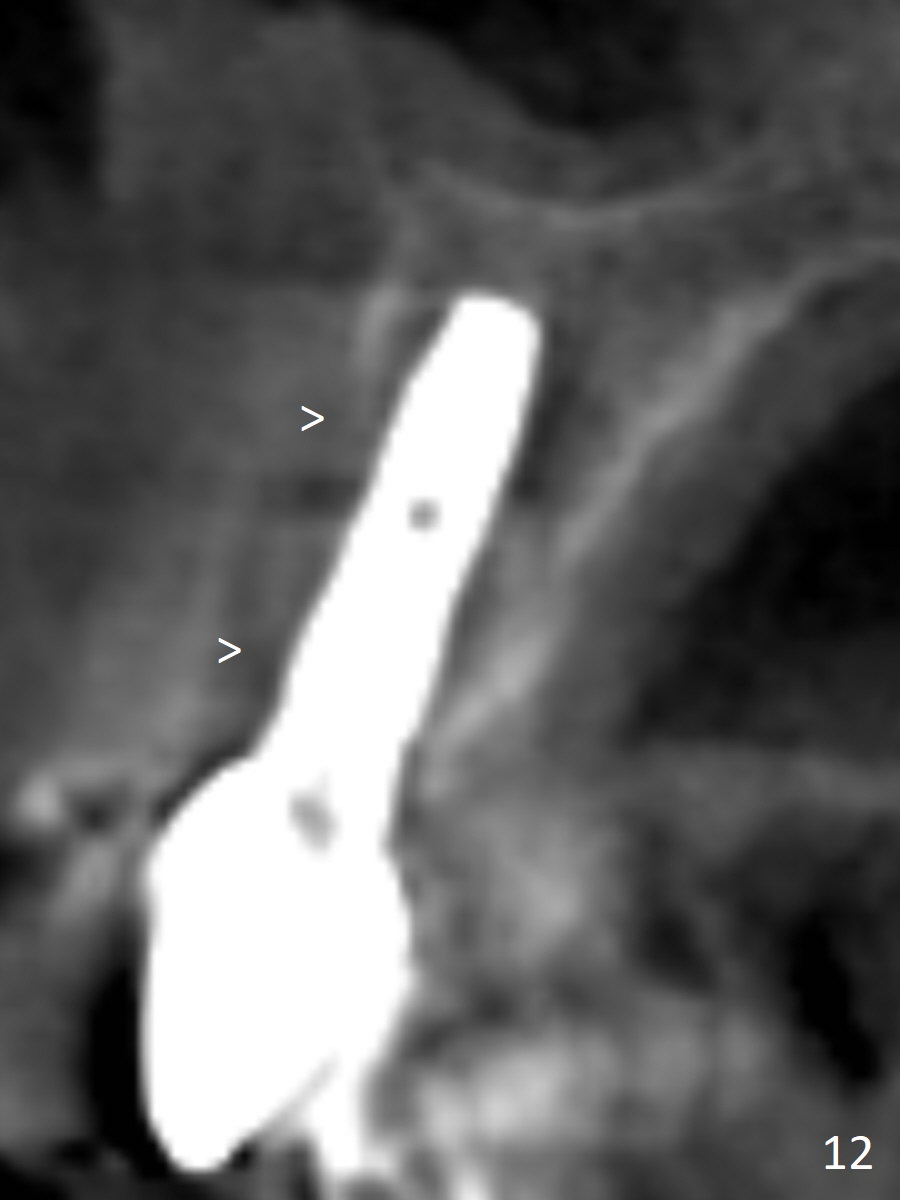

The gingiva adapts well to the provisional 1 week postop (Fig.8). The buccal gingiva remains recessive and the buccal plate is concave 5.5 months postop (Fig.9-11). It appears that the coronal portion of the buccal plate is resorbed 12 months postop (6 months post cementation, Fig.12 >). Socket shield or smaller diameter implant should have been done to avoid bone loss. Reanalysis of CBCT reveals that implantation apparently increases the bone width and that the buccal plate resorption is not so severe (Fig.13,14 (>: coronal end of the buccal plate)). Panoramic X-ray is taken 2 year 5 month post cementation.